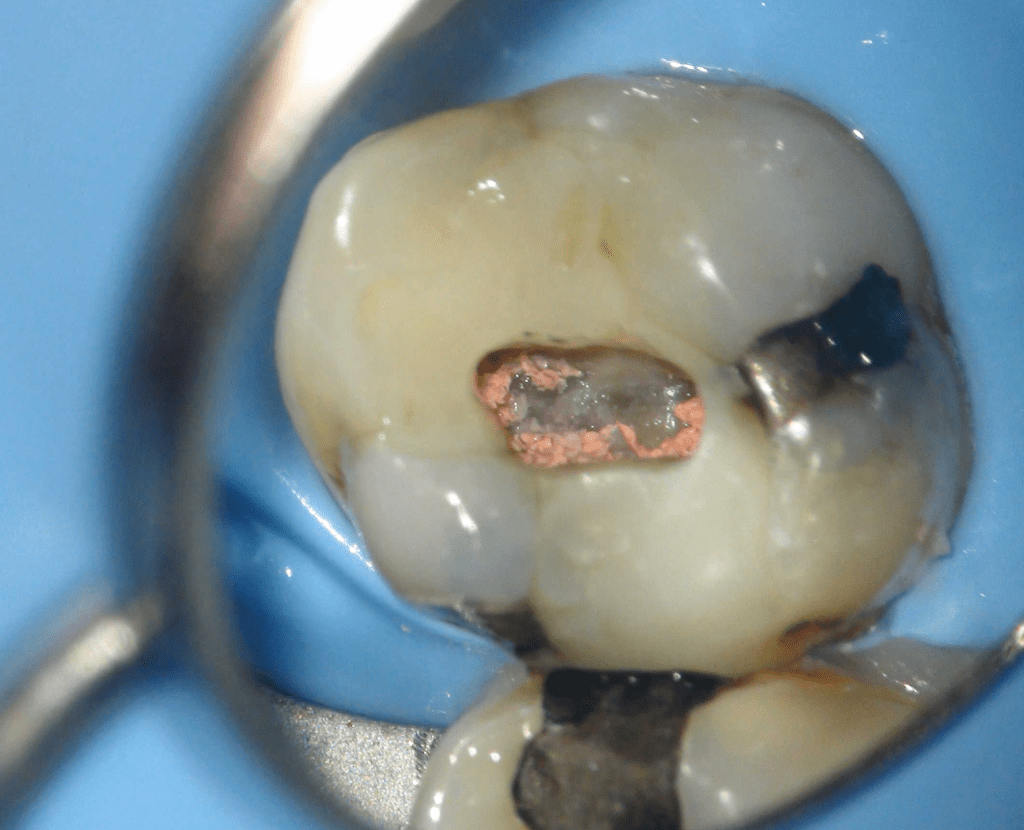

Fisura, remoción amalgama para explorar

Fractura cuspídea tratable